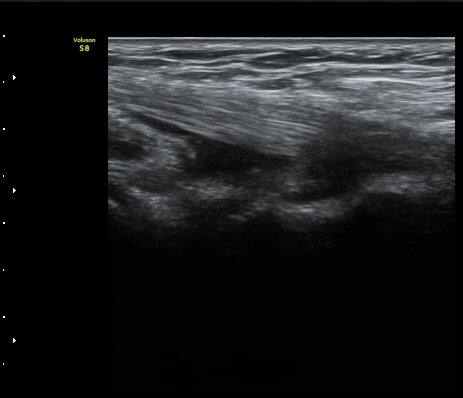

ÆÈ²ÞÄ¡ µÚÂÊ °üÀý¸éÀ¸·ÎºÎÅÍ 2.5cm ¾Æ·¡¿¡¼­ ¿ä°ñ°ü°ú ô°ñ °æ°èºÎ¸¦ Ⱦ´Ü¸éÀ¸·Î

°Ë»çÇÏ´Ï ¿ä°ñµÎ¿¡ ºÎÂøµÈ À̵ιڱ٠ÈûÁÙÀÌ °üÂûµÈ´Ù(±×¸² 9). Á¾´Ü¸é°Ë»ç¿¡¼­µµ

À̵ιڱ٠ÈûÁÙ°ú ¿ä°ñµÎ°¡ ¶Ñ·ÈÈ÷ °üÂûµÈ´Ù(±×¸² 10).

ÃÊÀ½ÆÄ°Ë»ç´Â À̵ιڱٺÎÂøºÎ °Ç¿° Áø´Ü¿¡ ¸Å¿ì À¯¿ëÇÏ´Ù.

À̵ιڱ٠ºÎÂøºÎ °Ç¿° ½Ã Áֻ縦 ÆÈ²ÞÄ¡ µÚ ¾Æ·¡¿¡¼­ ½ÃÇàÇ϶ó´Â

Dr. Cyriax ÀÇ À§´ëÇÑ °¡¸£Ä§À» È®ÀÎÇÏ´Â ¼Ò°ßÀÌ´Ù.